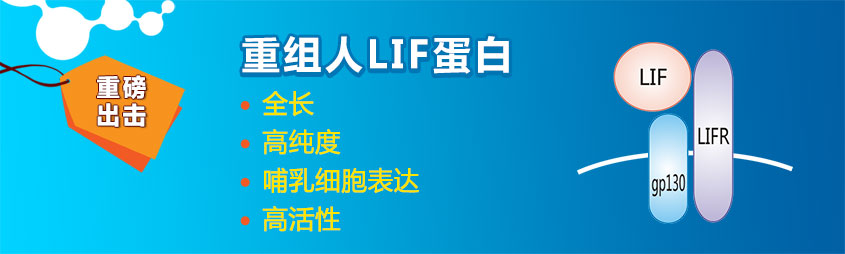

LIF(Leukemia Inhibitory Factor)細胞因子,對于腫瘤的發展和治療具有一定的作用。LIF在人體中通過與其受體結合而發揮生物學功能。

查看詳情